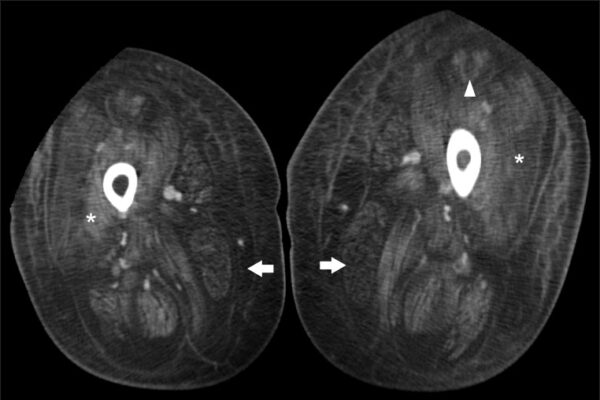

- Magnetic resonance imaging of the breast